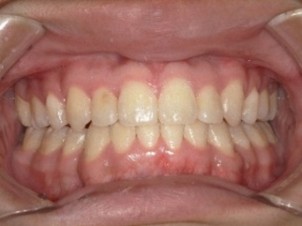

(↑マウスピース矯正後)

1~2か月毎にワイヤー矯正と同様に経過観察に来ていただきます。上の写真がマウスピース矯正後の口腔内です。きれいな歯並びになりました!